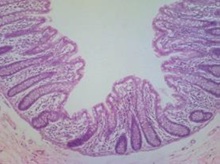

- Digestive System